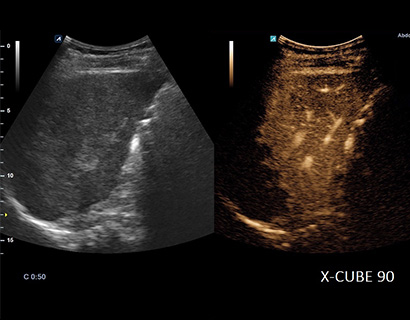

SC1-7H

X+ Crystal Signature™ convex transducer(1~7MHz)

Application:

Abdomen, EM, Gynecology, Obstetrics, Pediatric, Urology